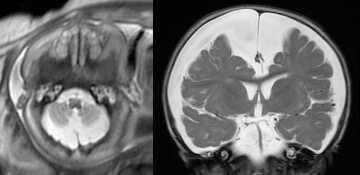

A : méga-grande citerne ; B : Dandy-Walker ; C : récessus pinéal ; D : porencéphalie - on demande également à l’imagerie de dire si le kyste est compressif ou non, ce qui est souvent difficile à déterminer. de nouvelles techniques d’imagerie comme l’ASL (Arterial Spin Labelling) sont encours d’évaluation dans la prise en charge des kystes arachnoïdiens.

les différentes techniques d’imagerie ont chacune des avantages et des inconvénients, et donc des indications respectives.